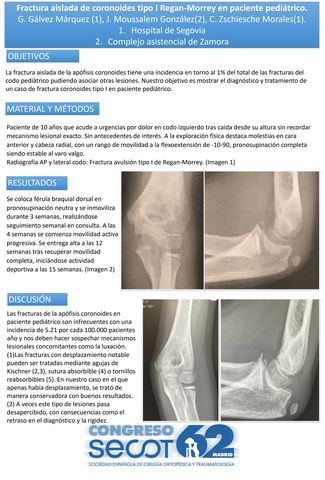

Fractura aislada de coronoides tipo I Regan-Morrey en paciente pediátrico.

GONZALO GÁLVEZ MÁRQUEZ, JORGE MOUSSALLEM GONZÁLEZ, CLARA ZSCHIESCHE MORALES